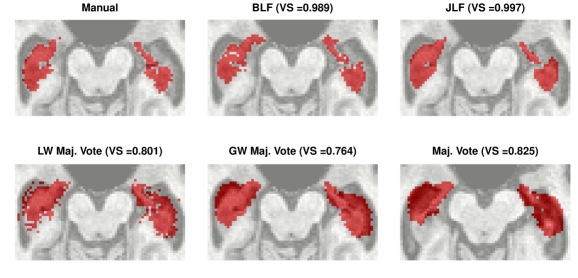

One can threshold the posterior probabilities to obtain a binary inclusion map. After thresholding, we compare the resulting segmentation to those obtained by simple majority voting, globally-weighted majority voting, locally-weighted majority voting, and JLF. The global weighting is inversely proportional to each atlas’ average intensity difference from the target. Local weighting is done similarly using voxel-specific intensity differences. Figure 9 displays one slice of the manual segmentation along with that which is obtained by thresholding the posterior inclusion probabilities at 0.5. The hippocampus is a relatively small structure compared to the full three-dimensional image (as can be seen in, e.g., Supplementary Figure 4). In this case, Taha and Hanbury (2015) argue that the Dice coefficient defined in Section 3 is not the best measure for evaluating a segmentation. However, the volume of the hippocampus is important for volumetry in the study of AD progression. Thus, we follow the suggestion of Taha and Hanbury (2015) and use the volume similarity as an evaluative metric, defined as , where and denote false negatives, false positives, and true positives, respectively. Bayesian label fusion attains . This is competitive with JLF, the current state-of-the-art (), and superior to both simple and weighted voting procedures. (VS values are displayed in Figure 9.)

As already mentioned, only healthy brains are used as atlases. The systematic differences are not completely captured by atlas-target image dissimilarities. Despite accounting for image dissimilarity, there is a tendency for the established methods to over-segment the hippocampus. The Bayesian label fusion model facilitates explicit incorporation of the estimated gray matter pattern as a predictor. Our prior specification allows for the possibility that the tissue classes are incorrectly assigned in some places, but are mostly reliable. The effect of the gray matter segmentation as auxiliary information can be clearly seen by comparing it even with our own model in which this information is ignored but the model is otherwise identical. Figure 10 displays the posterior inclusion probabilities obtained without using the gray matter information, along with the results already presented for reference. Using only the intensity-similarity-weighted distance labels yields a Bayesian regression analogue to the other approaches that only weight by intensity similarity. The additional tissue class information is able to prevent oversegmentation of the diseased structure.